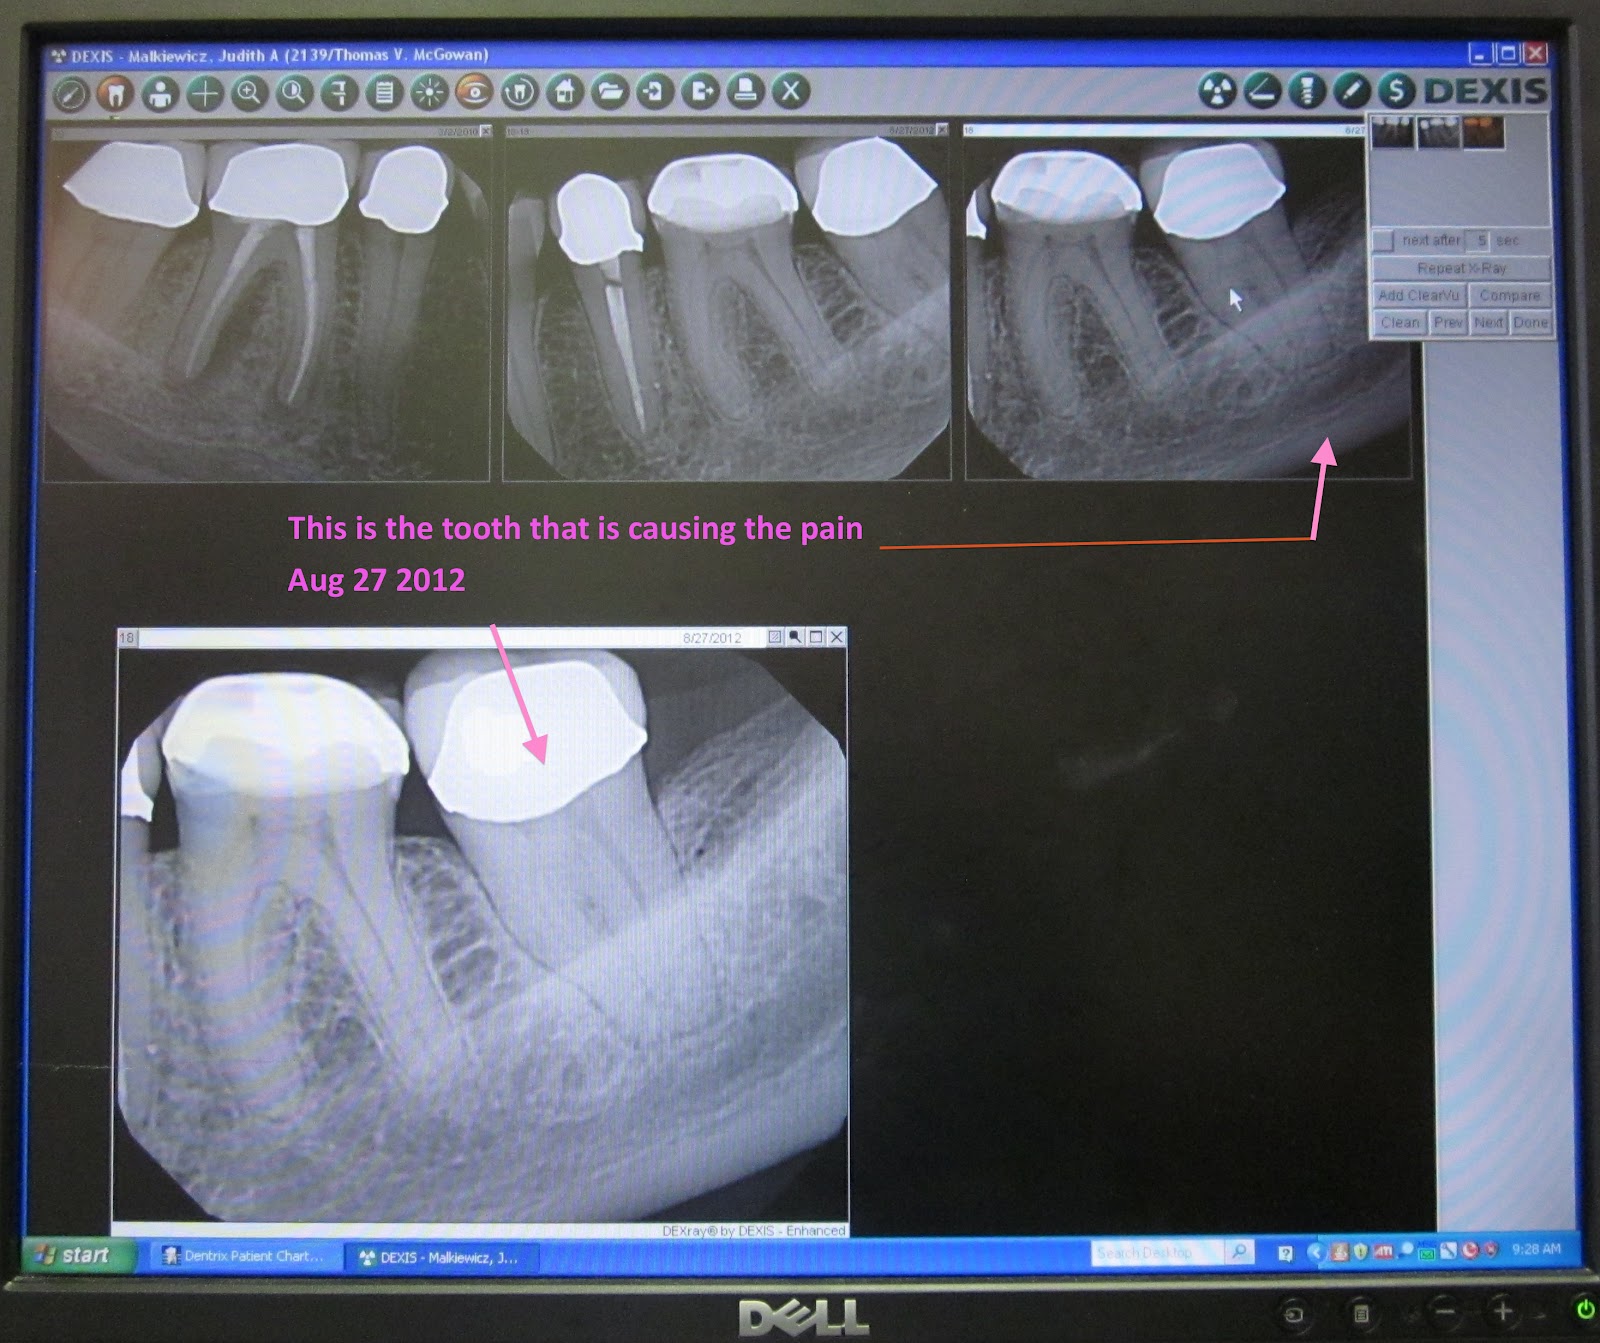

From jmmultiplemyeloma.blogspot.com

jm's Adventure with Multiple Myeloma 2nd ASCT Day 101 August 27 2012 Challis Dentist Some popular services for dentists include: Mcgowan is a dentist in challis, idaho. He provides advice on proper brushing, flossing, cleaning, healthy gums,. Mcgowan works in challis, id and specializes in dentistry. Thomas mcgowan, dmd is a dentistry practitioner in challis, id. what are some popular services for dentists? compare dentist in challis, id. Richard stoker is located. Challis Dentist.